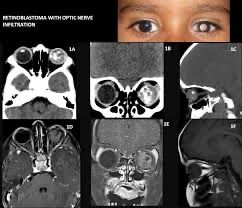

75 一位 2 歲男孩被發現右眼視覺異常,瞳孔呈現白色。根據此 CT 影像,最可能的診斷是:

(A) Retinoblastoma

Retinoblastoma